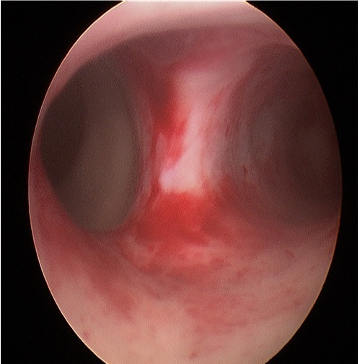

3)Histeroskopik sineşi açılması veya adezyolizis

Geçirilmiş myom ameliyatı, doğum sonrası kürtaj veya sezaryen gibi ameliyatlardan sonra ve rahim tüberkülozundan sonra rahim iç tabakasında yapışıklıklar oluşabilir. Bu hastalarda adet hiç olmayabilir, adet kanaması normalden az olabilir. Adet döneminde şiddetli ağrı olabilir. Yapışıklık çok az olsa bile hastalar gebe kalamayabilir veya düşük olabilir. Çocuk sahibi olmak isteyen hastalarda tedavi histeroskopi ile yapışıklıkların açılmasıdır.